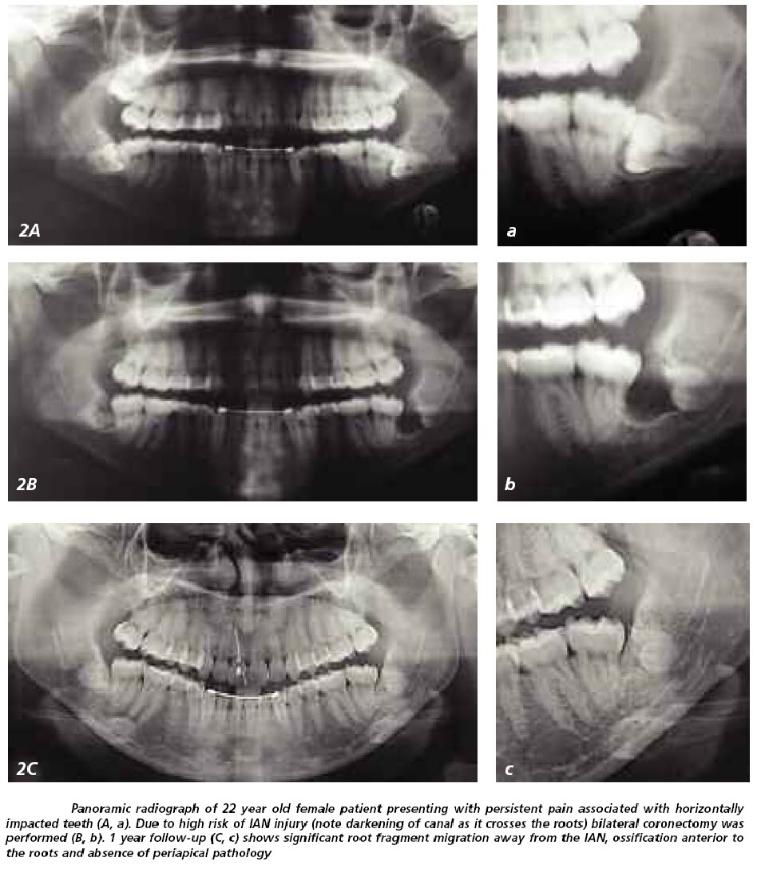

Coronectomy is the removal of the crown of a tooth, leaving the roots in situ.

When applied to a lower wisdom tooth or any lower unerupted posterior tooth, it is a procedure used to avoid damage to the Inferior Alveolar Nerve (IAN) (the nerve that supplies feeling / sensation to the lip and chin) when the X-ray has suggested an intimate relationship between the roots of the lower wisdom tooth and the IAN (the intimacy of the tooth roots to the nerve canal can be confirmed with the use of a Cone Beam CT scan [CBCT]).

Root Migration.

Subsequent migration of the roots away from the IAN occurred in 14 – 81% of cases. The roots seem to move the most during the first 6 months post-coronectomy, with a typical distance of 2 – 3mm away from the IAN. Root migration halts as the bone regenerates and remodels.

This can happen in up to a 2 – 6% of cases. If the roots irritate overlying tissues or the adjacent tooth or otherwise become symptomatic, they may need to be removed. Even though a 2nd surgery would be needed, the possibility of nerve damage should be negligible since the roots would have migrated away from its original resting place next to the IAN. Since the purpose of the coronectomy is to avoid this damage, this goal would have been accomplished even though a 2nd surgical procedure was necessary to remove the remaining root.